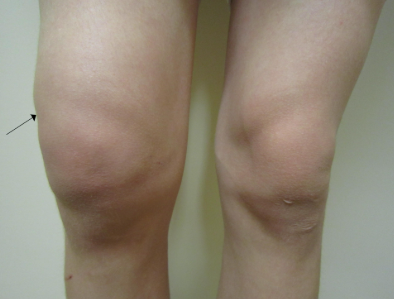

무릎 부기와 팽윤(부풀어 오름)

무릎 부위 발적, 열감 (염증이나 감염 시)

신체검사와 병력 청취

영상검사: 엑스레이, 초음파, MRI 등으로 관절 상태 확인